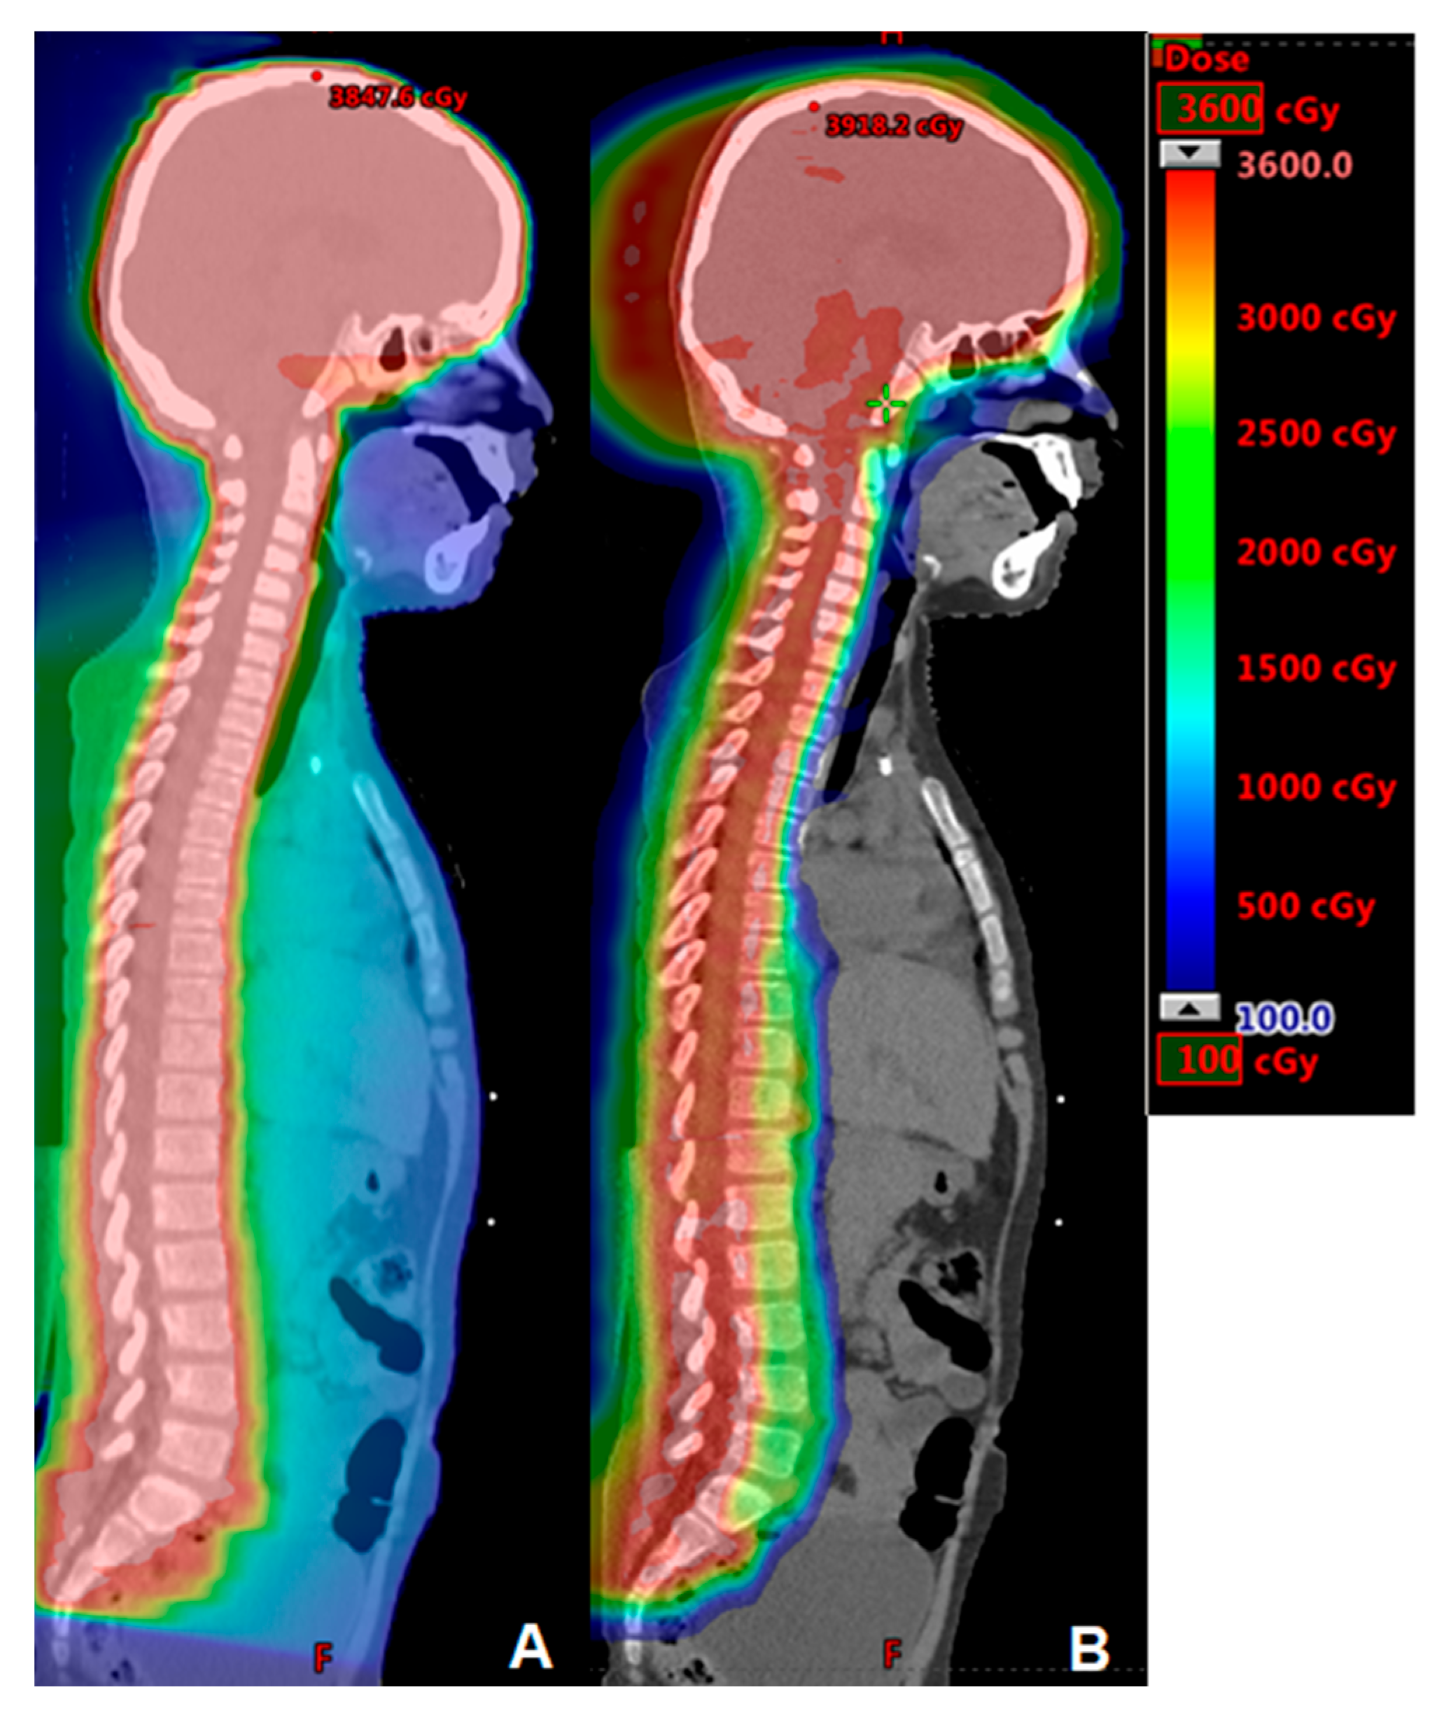

2. Central Nervous System Tumors

5. Hodgkin Lymphoma

- Dabaja, B.S.; Hoppe, B.S.; Plastaras, J.P.; Newhauser, W.; Rosolova, K.; Flampouri, S.; Mohan, R.; Mikhaeel, N.G.; Kirova, Y.; Specht, L.; et al. Proton therapy for adults with mediastinal lymphomas: The International Lymphoma Radiation Oncology Group guidelines. Blood 2018, 132, 1635–1646. [Google Scholar] [CrossRef]